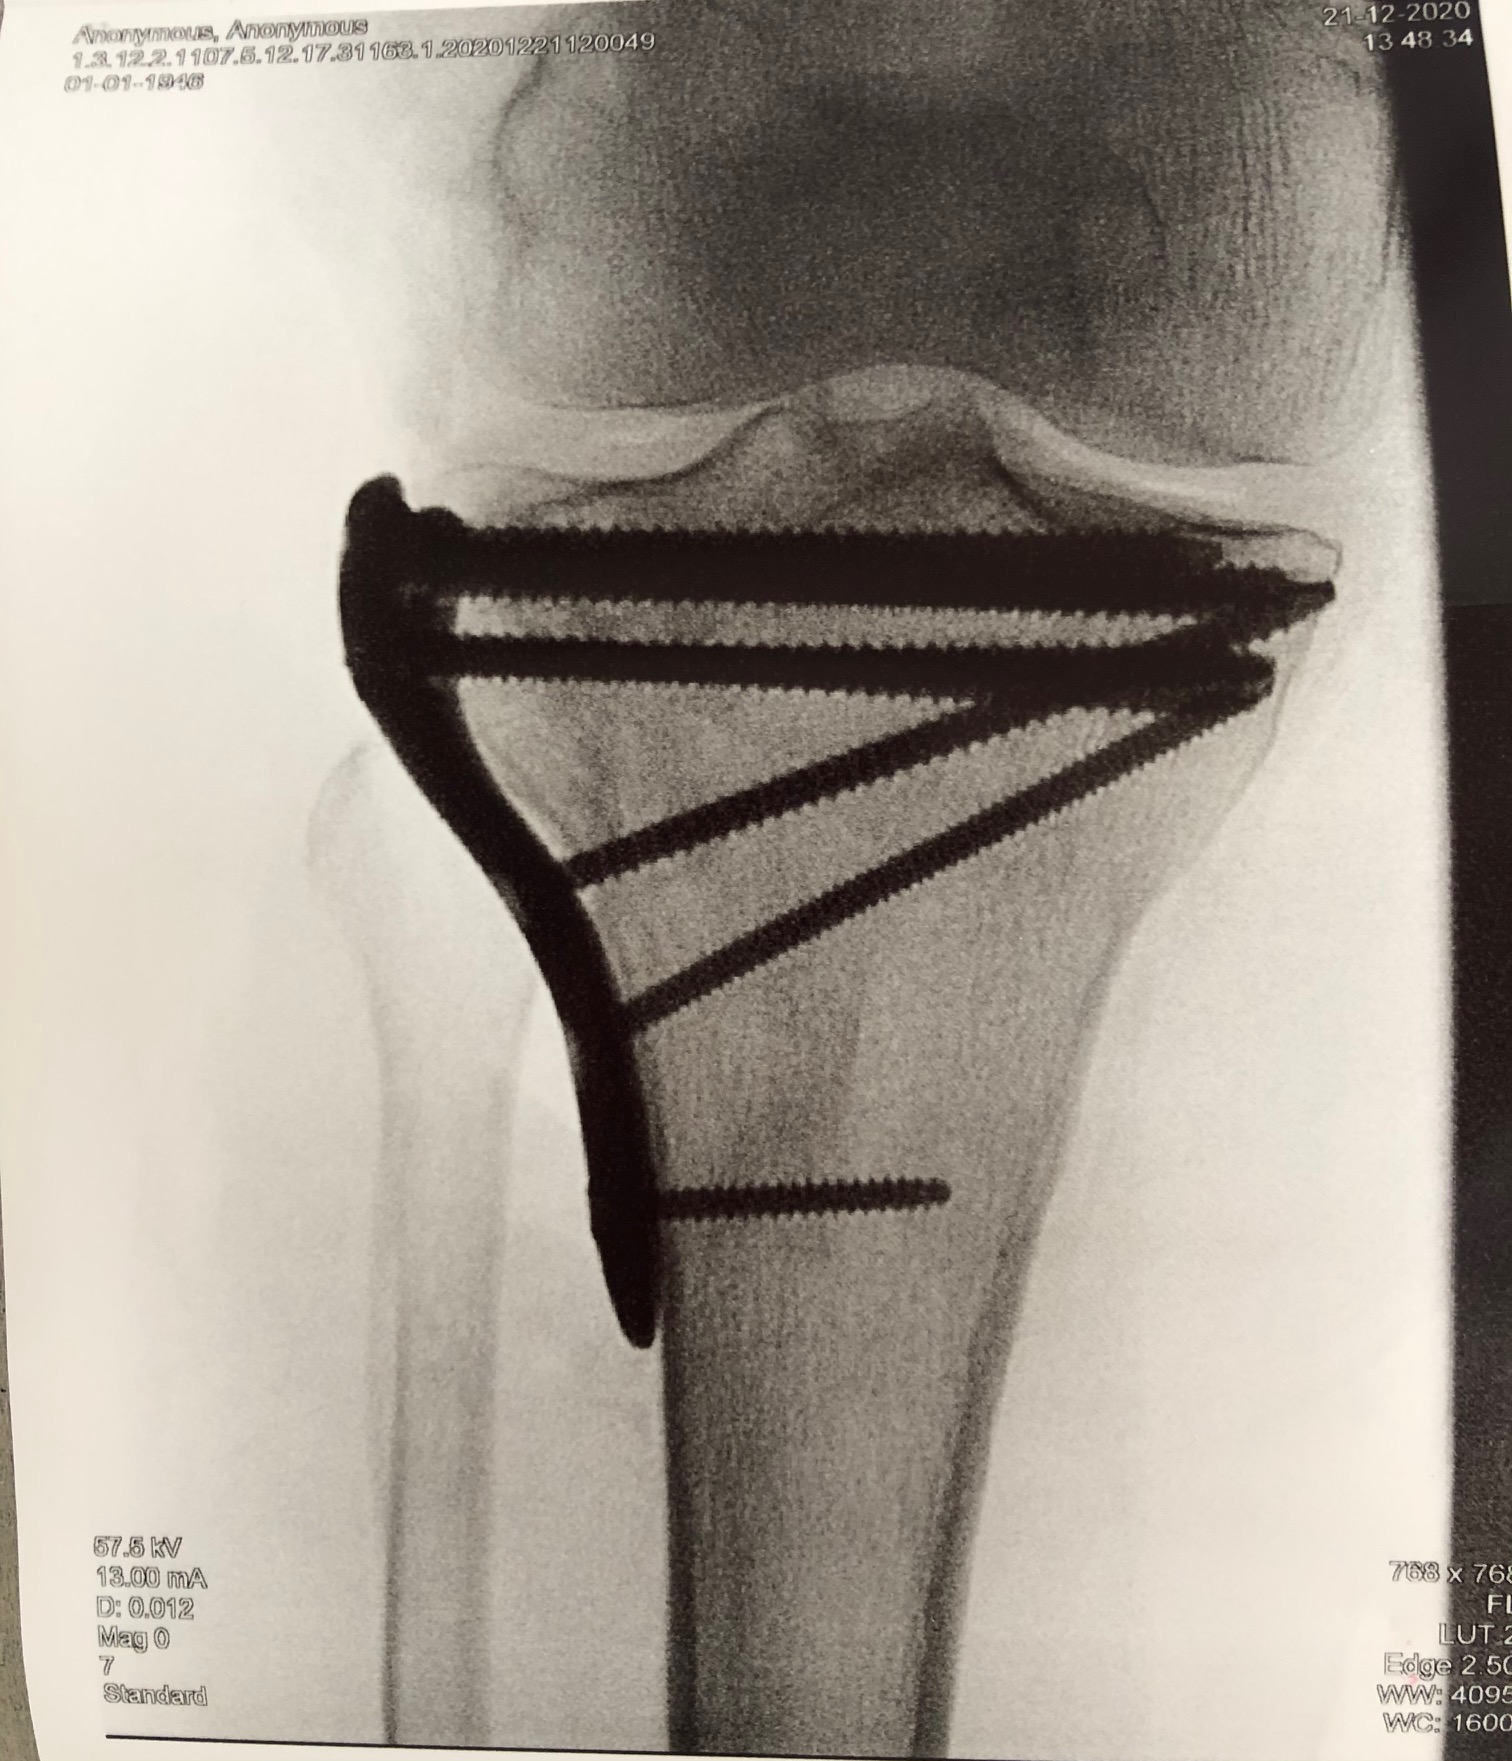

Η διάγνωση ενός κατάγματος κνημιαίου plateau πραγματοποιείται από έναν έμπειρο Ορθοπαιδικό. Αρχικά η λήψη ενός λεπτομερούς ιστορικού και η κλινική εξέταση του ασθενούς είναι απαραίτητα. Στην συνέχεια για την διάγνωση αλλά και την ταξινόμηση του κατάγματος είναι υποχρεωτική η διενέργεια ακτινολογικού ελέγχου. Ο έλεγχος αυτός περιλαμβάνει απλές ακτινογραφίες (φας, προφιλ και λοξές) ενώ πολλές φορές απαιτείται περαιτέρω διερεύνηση με αξονική τομογραφία για την πλήρη κατανόηση της μορφής του κατάγματος και τον σωστό προεγχειρητικό σχεδιασμό.

Σε κατάγματα του κνημιαίου plateau με μεγάλη συντριβή, με εμβύθιση της αρθρικής επιφανειας ή σε ασθενείς με αθλητική δραστηριότητα συστήνεται η χειρουργική αντιμετώπιση. Αυτή συνίσταται στην ανοικτή ανάταξη του κατάγματος και την εσωτερική οστεοσύνθεση του (τοποθέτηση πλάκας και βιδών), την τοποθέτηση εξωτερικής οστεοσύνθεσης ή στον συνδυασμό μεθόδων. Σε επιλεγμένα περιστατικά μπορεί να γίνει η ανάταξη του κατάγματος υπό αθροσκοπικό έλεγχο.